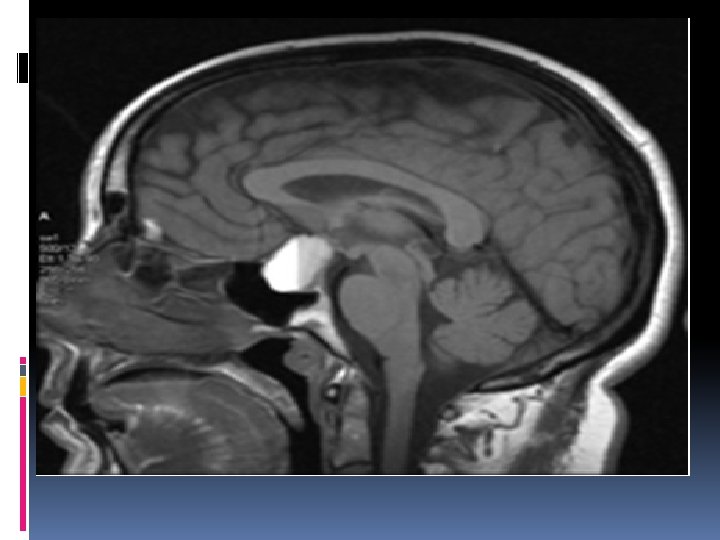

Pituitary apoplexy Acute haemmorrhagic necrosis of a pituitary adenoma&adjacent pituitary tiss. Predisposing factors: pregnency, endocrinologic manipulations(estrogen adminstration, bromocriptine medication), H. injury, chronic cough&sneezing, anticoagulant drugs, cerebral angio. , radiotherapy

Symptoms &signs Headache, nausea & vomiting, diplopia&visual impairment, compression of cranial n. s in one or both cavernous sinuses, ophthalmoplegia, meningeal irritation, photophobia Diagnosis(MRA, ANGIO, CT, CLINICAL) Treatment : surgery